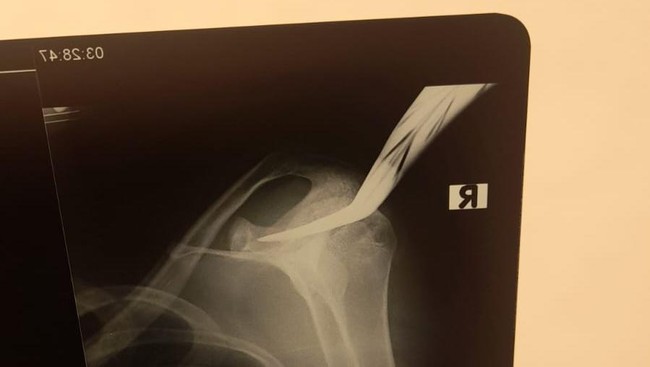

Hasil rontgen celurit nancap di bahu ojol korban pembacokan di Jalan Pemuda, Bantul, Minggu (2/6/2024). (Foto: dok. Polres Bantul)

Seorang remaja ojek online (ojol) berinisial TS (17) menjadi korban pembacokan di Jalan Pemuda, Teruman, Bantul, dini hari tadi. Mirisnya celurit pelaku masih tertancap di bahu korban saat dibawa ke rumah sakit.

Jeffry menyebut korban kini tengah dalam penanganan medis. Luka bacokan masuk ke tulang skapula, tepatnya bahu sebelah kanan dengan luka 4 sentimeter.